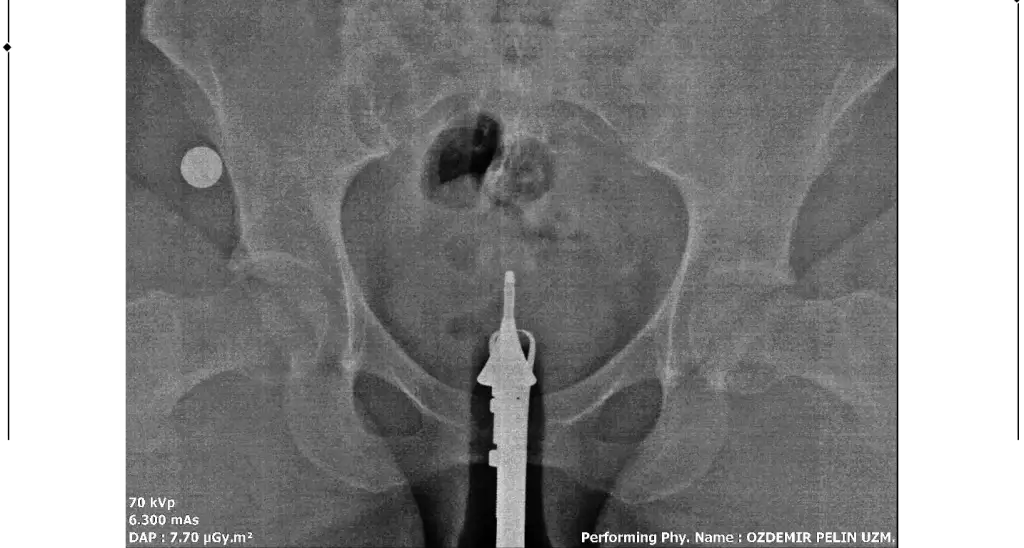

Merhaba, sağlıklı rahim gorseli ile kiyaslaninca sanki üstten biraz basık ama endişelenmeyin benim direk Y di belki çekim açısından olabilir, sizde sadece tüpleri anlayamadim dağılmış sanki açık tikaniklikda yok gibiMerhaba benim rahim filmim bu şekilde bir rapor oluşturulmadı filmi bugün çekildim doktora da gosteremedim. Yorumlanabilir misiniz?

Çok teşekkür ederim cevabınız içinMerhaba, sağlıklı rahim gorseli ile kiyaslaninca sanki üstten biraz basık ama endişelenmeyin benim direk Y di belki çekim açısından olabilir, sizde sadece tüpleri anlayamadim dağılmış sanki açık tikaniklikda yok gibi

Sizin yorumunuzu görünce bende hidrospenks baktım da sanki sağ tarafta boğum var gibi ama tek tüple de gebelik oluşuyor zaten benimde tıkalı malesef, yinede endişelenmeyin sakın korkuyorumda yorum yaparken yanlış anlaşılırim üzerim diyeGenişleme olabileceği söylendi yani sıvı olabilir dendi. Hidrosalpenks oluyor o var gibi geldi sanki bana

Anlayışınız için çok teşekkür ederim. Bakalım doktora gösterince net sonucu öğrenirim. Çok teşekkür ederim tekrardan.Sizin yorumunuzu görünce bende hidrospenks baktım da sanki sağ tarafta boğum var gibi ama tek tüple de gebelik oluşuyor zaten benimde tıkalı malesef, yinede endişelenmeyin sakın korkuyorumda yorum yaparken yanlış anlaşılırim üzerim diye

Merhaba bana da hidroselpenks gibi geldi çok hafif boğum var doktorunuzun yorumu ne oldu acabaMerhaba benim rahim filmim bu şekilde bir rapor oluşturulmadı filmi bugün çekildim doktora da gosteremedim. Yorumlanabilir misiniz?